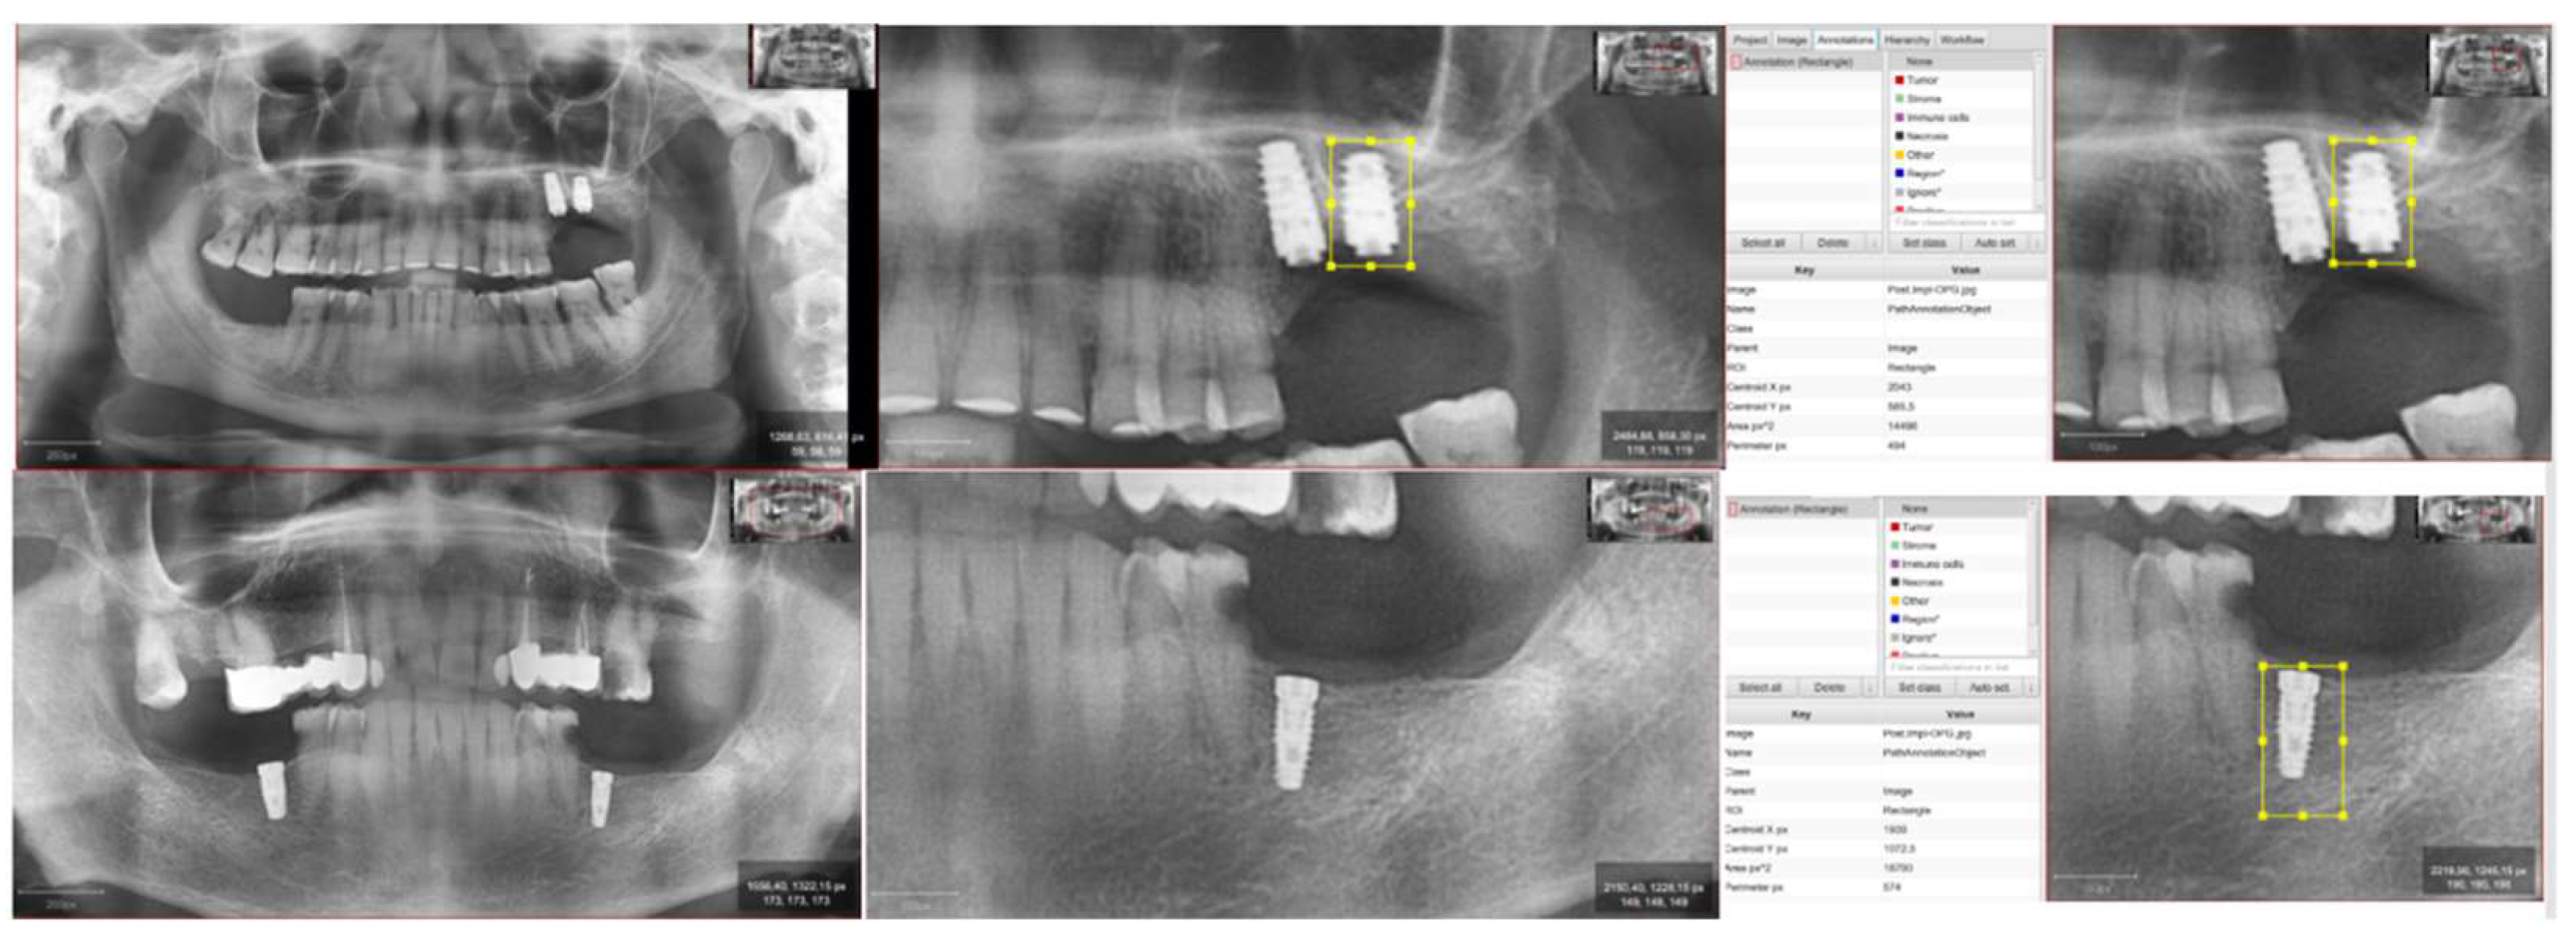

2.3. Obtaining Images and Processing

- Diagnostic or pre-implantation phase, CBCT obtained before the surgical procedure.

- Post-implantation phase, CBCT obtained after implant placement and with prosthetic load.

2.4. Fractal Dimension Analysis